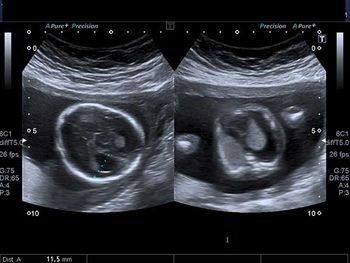

What is your diagnosis of this major pathology in a second trimester fetus?